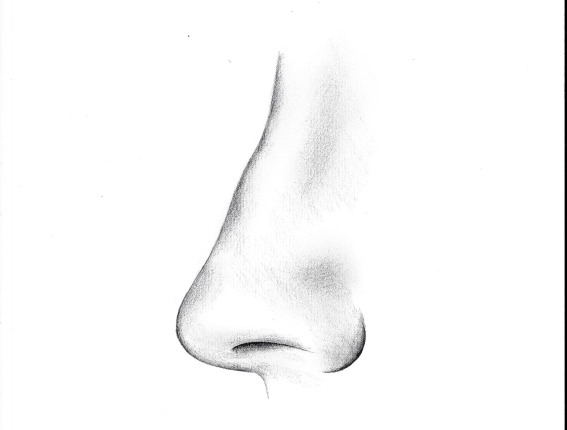

EPITHESE NASALE

Une épithèse nasale est une prothèse utilisée pour remplacer tout ou une partie du nez, en particulier pour des raisons esthétiques et psychologiques, tout en permettant au patient de se sentir plus en harmonie avec son image corporelle.